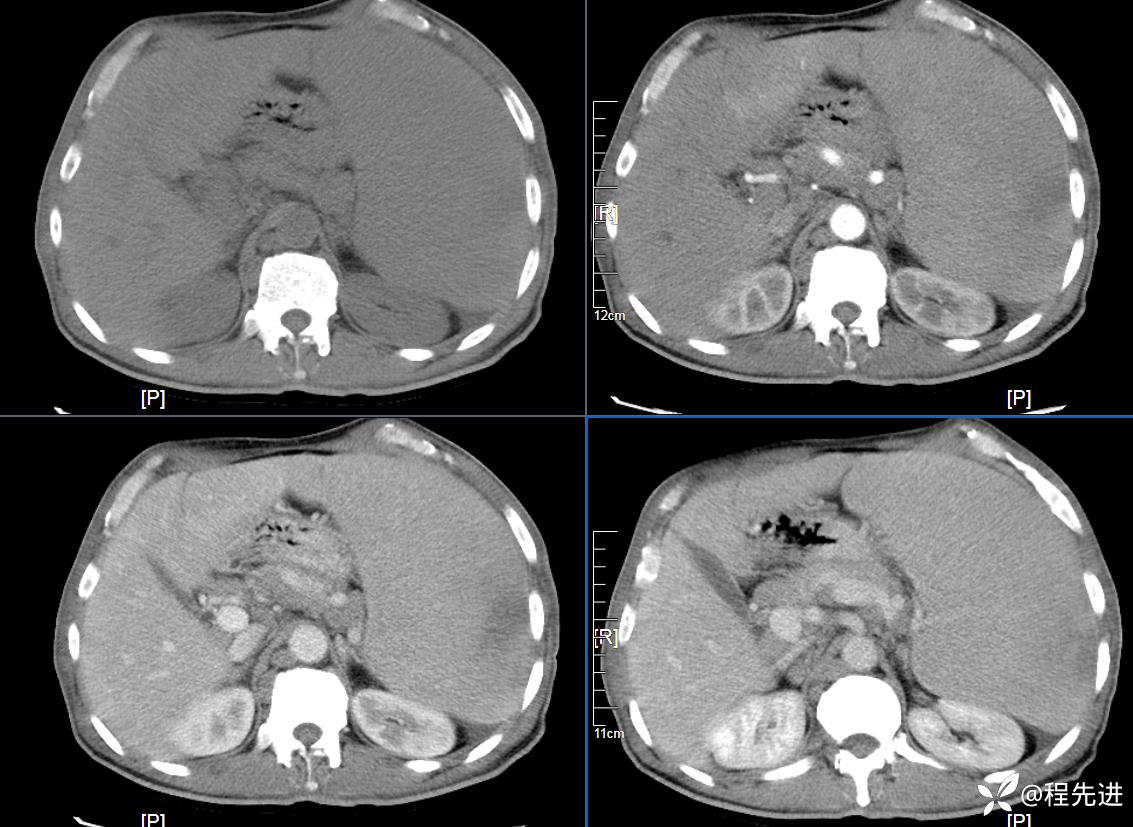

患者性别:男

患者年龄:59岁

简要病史:体检发现脾脏肿大半月

CT平扫及增强3期: